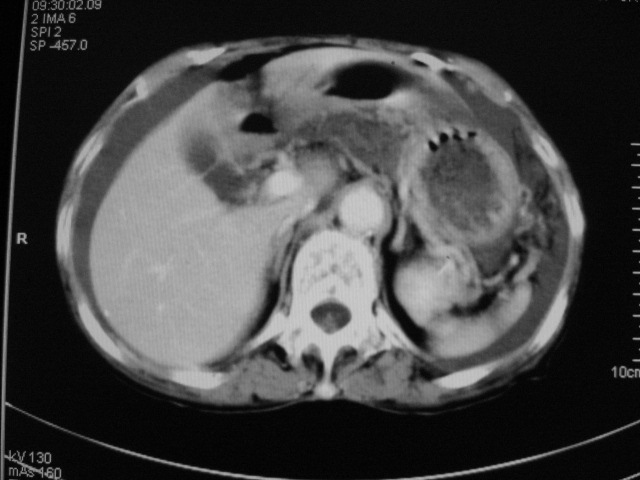

以下是引用默契在2007-9-20 17:29:00的发言:[br][br] [br] 考虑:1、胆囊占位性病变(以癌可能性大);[br] 2、中量腹水。 [br] [br]

以下是引用快乐男生在2007-9-20 15:32:00的发言:[br]图像质量不好:[br]胆囊增大,囊壁增厚,[br]可见结节突出囊腔内,[br]增强后与囊壁相仿.[br]考虑多为胆囊慢性炎症伴有胆囊体部的息肉